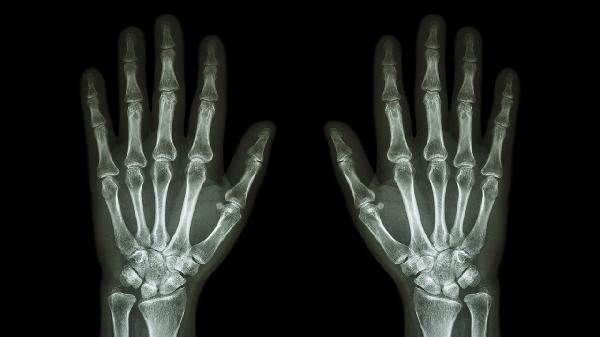

手指关节肿胀初期可进行冰敷处理,每次15-20分钟,间隔2小时重复。48小时后改为热敷促进血液循环。恢复期间应避免患指过度活动,可佩戴指套保护。饮食注意补充优质蛋白和维生素C,有助于组织修复。若肿胀持续超过3天或伴有明显畸形、活动障碍,需及时就医排除骨折可能。日常运动前做好充分热身,佩戴运动护具能有效预防手指戳伤。